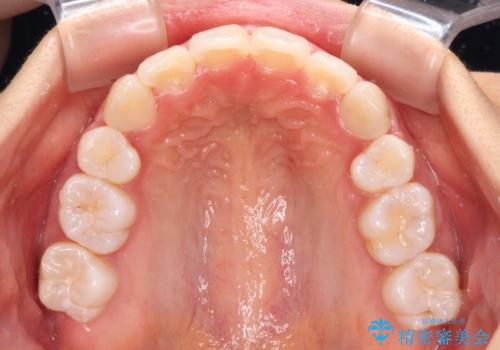

口元の突出感を改善 2年弱での抜歯矯正

治療前の上下正中はずれていましたが、骨格的な上下左右差はあまり認められなかったため、正中を揃えて治療を終えることができました。

1年半ほどで治療を終えることができるとは我々も想像しておらず、患者様には大変満足していただきました。